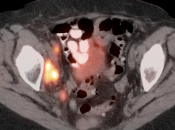

Cervical Cancer

Fast Facts:

- 2nd most common cancer in women worldwide

- Localized Disease: 5-year survival: 91%

- Distant Disease: 5-year survival: 16%

- Squamous cell carcinoma > 90%

- Adenocarcinoma 5-9%

Initial Staging:

- Valuable diagnostic tool for locally advanced disease, to determine nodal status and potential distant metastatic disease (if no evidence of regional or distant disease, initial management is surgical).

- PET/CT has high sensitivity (>80%) and high specificity (>90%) for metastatic lymph nodes ≥ 8.0 mm.

The size, metabolic activity & location of the primary lesion and representative metastatic lesions are reported.

Primary Lesion:

- Nearly every cervical cancer ≥ 8.0 mm is intensely FDG avid (MRI, however, is still considered the best modality for evaluating tumor size and invasion).

Metastatic Disease:

- Direct invasion of adjacent structures.

- Lymphatic spread to pelvic and retroperitoneal lymph nodes.

- Hematogenous spread, often to lungs, liver, and bone.